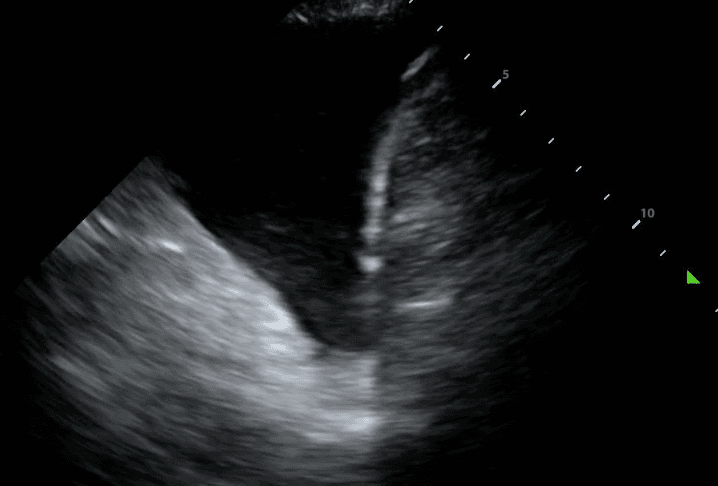

Next, identify the patient’s liver (if your probe is on the right side) or spleen (if your probe is on the left side). Above that, you will see a thin, hyperechoic line which is the patient’s diaphragm.

Finally, above the diaphragm, you will see one one of two things: if there are normal lungs without a pleural effusion, you will see an aerated lung obscuring the diaphragm during inspiration. This is referred to as a “curtain sign.”

If a pleural effusion is present, there will be an anechoic (ie. black) space above the diaphragm. Please note that an anechoic space below the diaphragm represents ascites; not a pleural effusion. Two other other features will stand out to you. Firstly, you will see a “spine sign.” Normally, the spine cannot be visualized above the diaphragm since aerated lung scatters ultrasound beams before it can reach the spine. However, a pleural effusion will allow sound waves to be transmitted to the spine and you will see the spine clearly visible above the diaphragm.